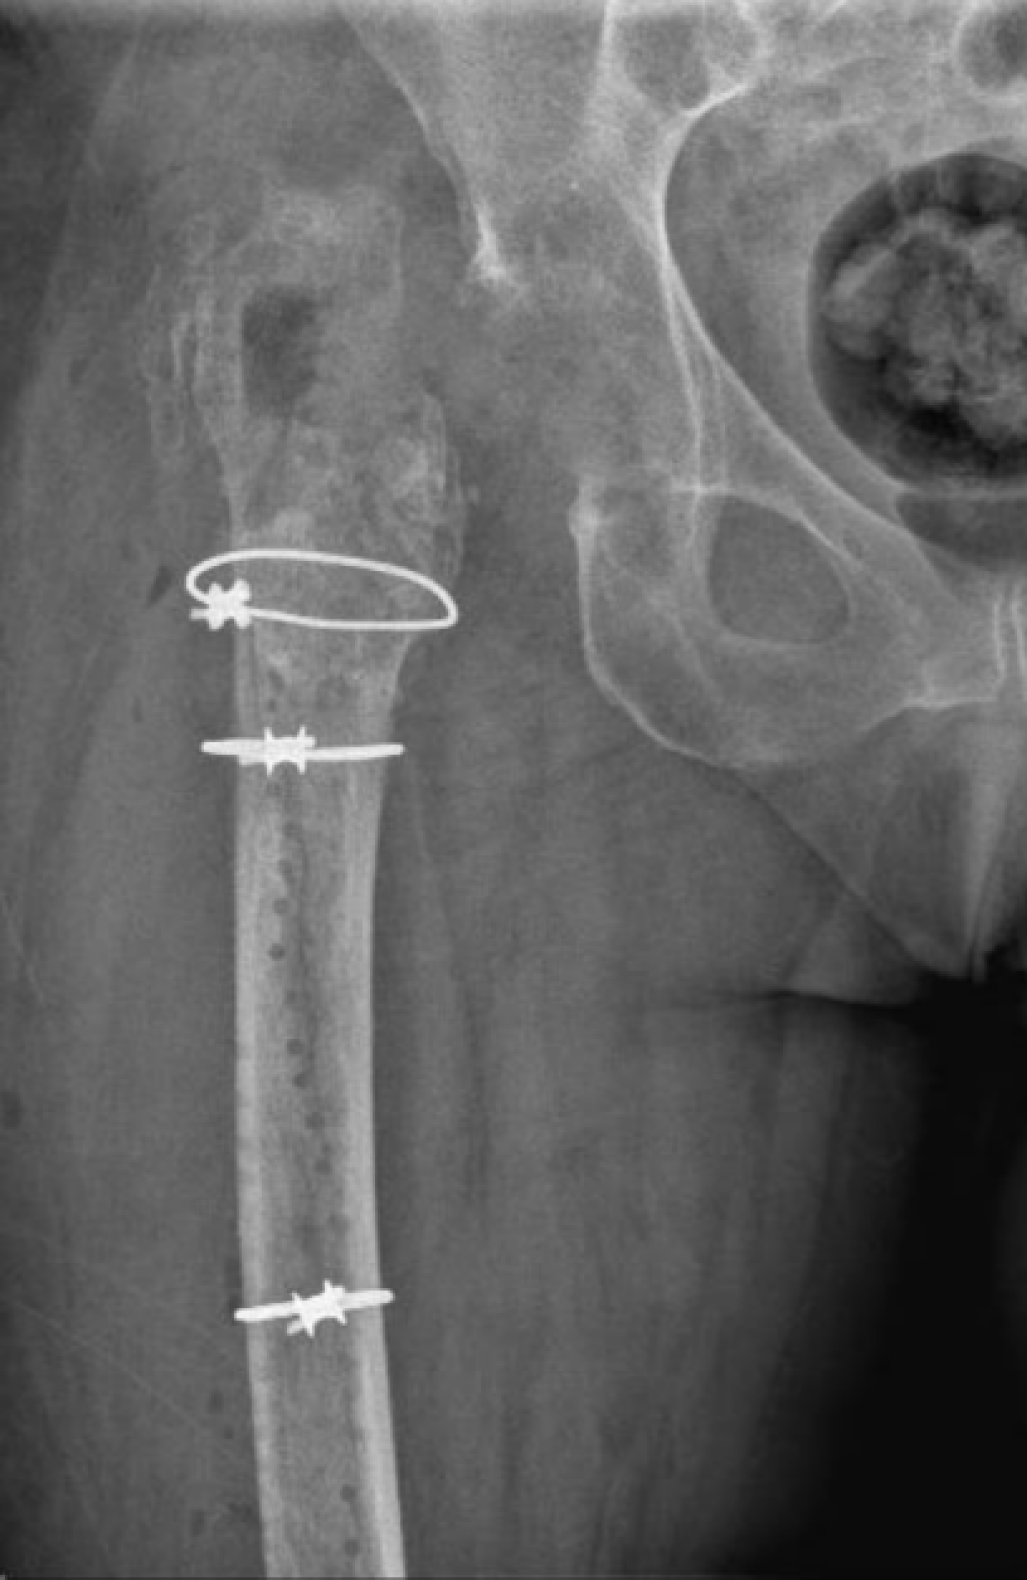

In the second cohort, from 2020 to 2023, a new protocol was introduced in our center (Group B). After the resection arthroplasty, a CUMARS (Figure 2) was created by coating commonly used femoral and acetabular components (Link® Lubinus Classic Plus Stem and Link® IP Acetabular Cup (Waldemar Link GmbH & Co. KG, Hamburg, Germany)) with antibiotic-loaded cement (Palacos® R+G bone cement, Heraeus Medical GmbH, Wehrheim, Germany), with additional antibiotics (1 g per batch of cement) tailored to the patient's specific pathogen (Figure 3). The spacer was then loosely implanted when the cement had a doughy consistency, ensuring easy removal during the second-stage surgery. Rotational stability of the CUMARS is achieved by folding the cement around the edges of the proximal femur and acetabulum. Patients were permitted partial weight-bearing (up to 50% of bodyweight) during the interval based on a recommendation by the operating surgeon. Patients were continuously treated with a minimum of 6 weeks of antibiotics following the first-stage surgery, including 2 weeks intravenously, up until reimplantation. After reimplantation, they received an additional 6-week course of antibiotics, with 1 week administered intravenously, totaling a minimum antibiotic duration of 12 weeks in total. In Group B, a Girdlestone interval was used in case a CUMARS was deemed contraindicated by the treating orthopedic surgeon intraoperatively based on bone stock and fracture risk. These patients received antibiotic treatment according to the protocol used in Group A.